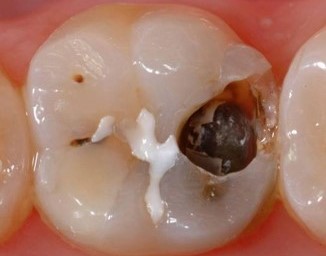

Using SDR® Plus has a number of advantages, including a reduced risk of postoperative sensitivity and enhanced marginal integrity, which is an important factor in the prevention of secondary caries. It also makes the creation of a uniform, void-free restoration easier thanks to the material's self-leveling qualities, and its high radiopacity simplifies monitoring of the restoration over time.

SDR® Plus is optimized for bulk filling posterior cavities that are challenging to access during a dental treatment. Unlike conventional filling materials, it is flowable and can be placed in up to 4 mm increments. This allows dental practitioners to fill a large portion of the posterior cavity in just one step with a flowable material that adapts itself to the cavity walls without further instrumentation. The unique chemistry of SDR® Plus also minimizes shrinkage stress that otherwise could lead to gap formation during light curing.